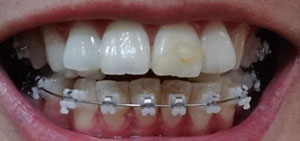

상악 왼쪽 오른쪽 어금니에 부착되어진 오라픽스 장치에 스프링 조절을 조금 더 해주었어요.

돌출된 치아를 밀어 넣기 위해서 발치공간 확보가 조금 더 필요한 상태인가봐요.

이번엔 정말 앞니를 밀어 넣겠지 하고 기대를 하고간거라 살짝 아쉬웠지만

하악에 파워체인 제거하고 와이어 교체했어요~

확실히 하악은 발치공간이 많이 닫힌거 같아요.

파워체인은 부착하지 않았고, 와이어만 교체해서 부착했어요.